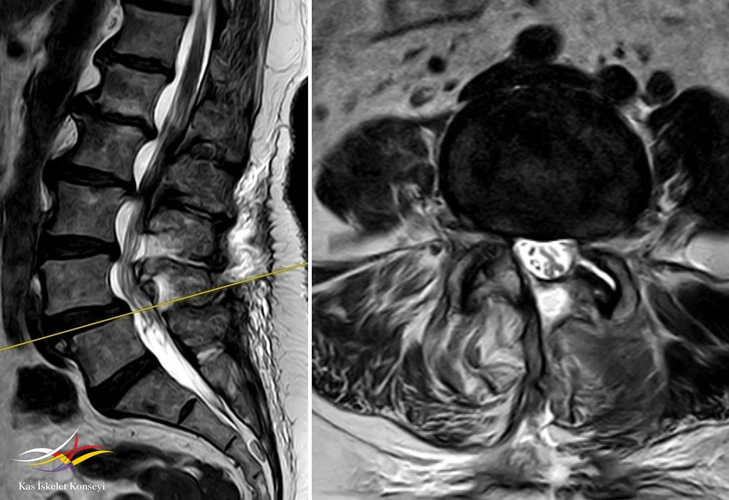

Resim 5. L4-5 seviyesinde dejeneratif listezis ve belirgin kanal darlığı görülmekte.

Resim 8. L4-5 seviyesindeki dekompresyon görülmekte.